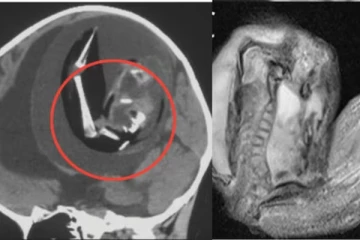

ஒரு வயது குழந்தையின் மூளைக்குள் இன்னொரு குழந்தை! 10 லட்சத்தில் ஒரு முறை நடக்கும் அரிய நிகழ்வு